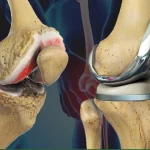

در تعویض مجدد مفصل زانو پروتز قبلی از مفصل خارج شده و پروتز جدید و مقاومتری جایگزین میشود. این عمل معمولاً پیچیدهتر از جراحی اولیه تعویض مفصل زانو است زیرا بافتها شرایط متفاوتی دارند و استخوانها ممکن است تراکم یا حجم خود را از دست داده باشند. هدف از این جراحی بازگرداندن ثبات، اصلاح درد، بهبود دامنه حرکتی و جلوگیری از آسیبهای بیشتر است.

اولین مرحله برای انجام این جراحی خارجکردن پروتز قبلی است که معمولاً با دقت زیادی انجام میشود تا کمترین آسیب به استخوانها وارد شود. این مرحله از جراحی نسبت به تعویض اولیه زمانبرتر و چالشبرانگیزتر است، زیرا پروتز به استخوان چسبیده است و خارج کردن آن نیازمند تخصص بالاست.

پس از برداشتن پروتز، جراح وضعیت استخوان را ارزیابی میکند. اگر نقص یا از بینرفتن حجم استخوان وجود داشته باشد، ممکن است نیاز به استفاده از گرافت یا قطعات پرکننده مخصوص باشد تا زمینه برای قرار دادن پروتز جدید فراهم شود.